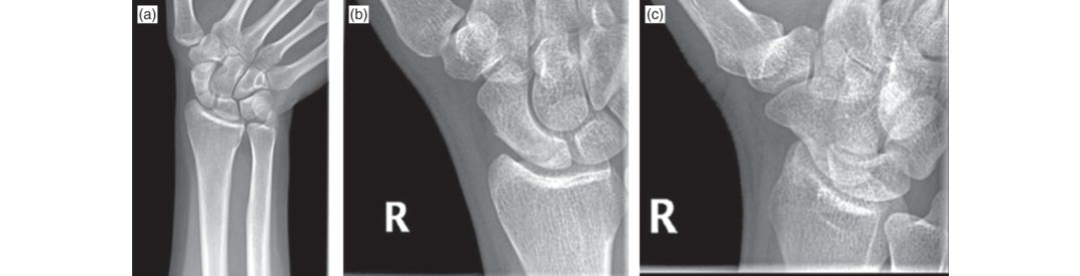

What is the diagnosis for a left-hand dominant woman, aged 38, who fell on her right arm and went to the accident and …